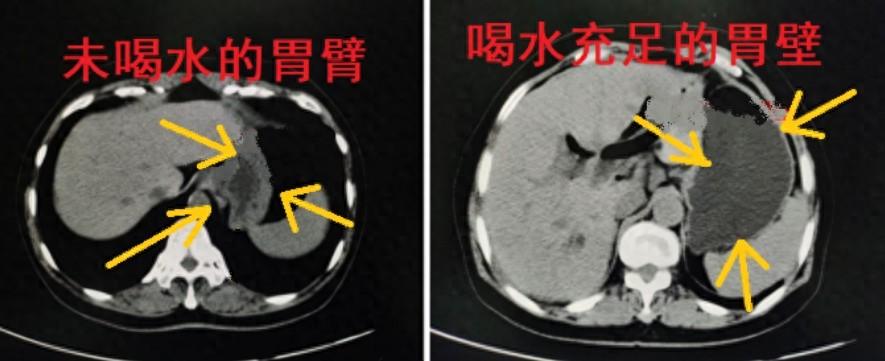

做CT腹部检查喝水能够起到撑开消化道管壁(图一)效果,这样使得管壁解剖结构显示更清晰,喝水憋尿充足也会使膀胱充盈,膀胱充盈后,膀胱腔内的病变和膀胱周围的器官可能会更清晰(图二),形成良好对比,便于放射科医生诊断。

(图一)